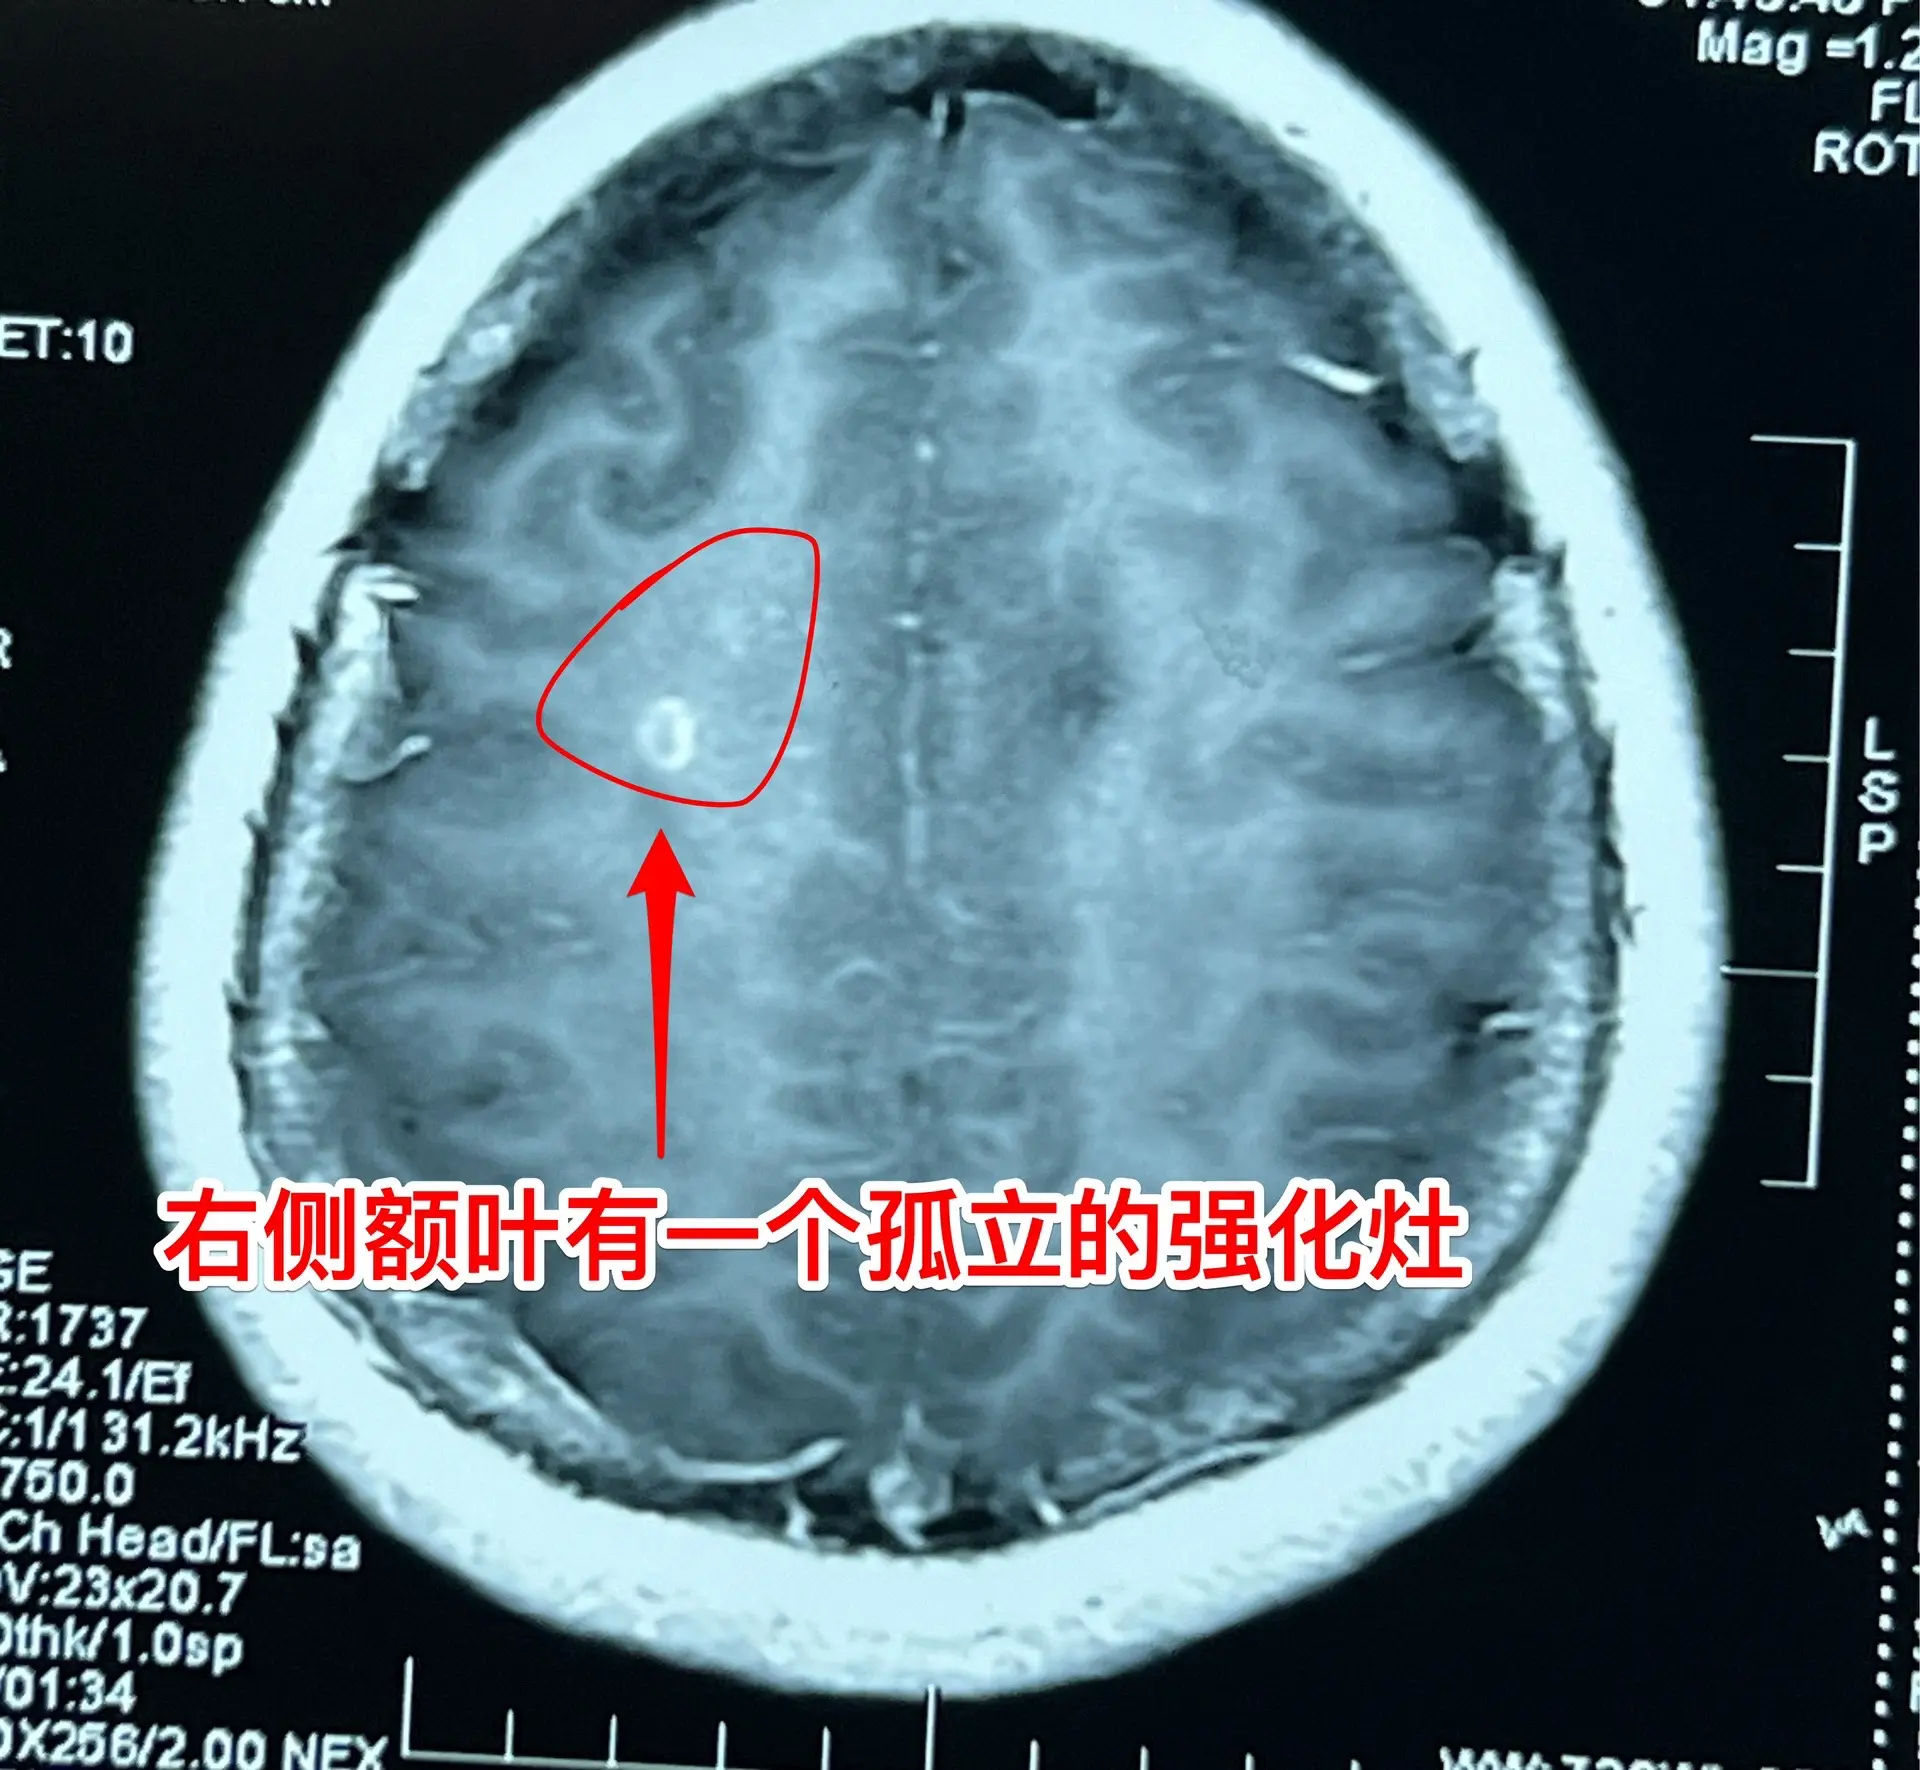

38岁女性脑部发现肿瘤、平时心跳很慢。38岁女性,西乌珠穆沁旗牧民,因头痛、呕吐10天,在锡林浩特市检查发现脑部肿瘤,遂到北京三博脑科医院来作手术。 脑部肿瘤见图,考虑是胶质瘤,肿瘤起源于胼胝体,胼胝体受肿瘤侵蚀,手术前病人的语言和智能没有明显障碍。 在手术准备过程中,发现 病人的心跳很慢,平常才41次/分,夜间最慢慢到31次/分。诊断为窦性心动过缓,为了确保手术安全,不得不临时安放心脏起搏器。 8月9日顺利完成肿瘤切除手术。手术过程很顺利。术中快速冰冻病理报告为胶质母细胞瘤。术后病人很快就清醒了。术后四肢活动无障碍,语言能力和智能情况需要详细评估。